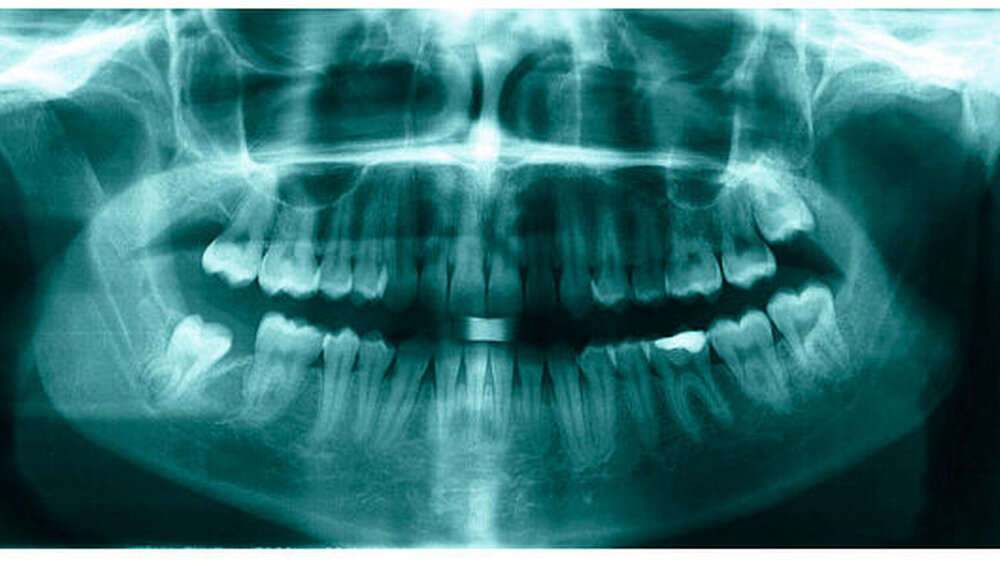

Bereits 2004 wies Carla Evans [Evans, 2005] auf das Risikomanagement bei Allgemeinerkrankungen hin und stellte am Beispiel der JIA dar, dass Unterkieferrücklagen und frontal offene Bisse aus der Kiefergelenkzerstörung entstehen können. Die Röntgenaufnahmen einer JIA-Patientin mit oligoartikulärer Form und Beteiligung des rechten Kiefergelenkes zeigen den typischen Verlauf sehr gut. Bei ursprünglich sehr dezenten Befunden, wie einer s-förmigen Mundöffnung von 44 mm, einer geringen Mittenabweichung um 2 mm nach rechts und einem frontal offenem Biss klagte sie über Schmerzen beim Essen, was den Anlass zur weiteren Diagnostik bot. Die erste Panoramaröntgenschichtaufnahme (Abbildung 1a-c) zeigt auf der rechten Seite einen abgeflachten Kondylus und eine bereits verstrichene Fossa condylaris. Ein Jahr später vermittelt das Fernröntgenseitenbild (Abbildung 1d) trotz fortschreitender kondylärer Resorption ein harmonisches Bild, während nach drei Jahren bei voranschreitendem Abbau des rechten Kondylus (Abbildung 1e) eine Rücklage der Mandibula und eine Bissöffnung manifest sind (Abbildung 1f).

Mithilfe der Panoramaröntgenschichtaufnahme lässt sich in bis zu 67 Prozent der Fälle bereits eine Kiefergelenkdestruktion bei Kindern mit JIA feststellen [Küseler et al., 1998; Twilt et al., 2004; Abramowicz et al., 2014]. Eigene Untersuchungen bestätigten die Eignung als Screening-Verfahren [Mäckelmann, 2008].

Bei 152 durchschnittlich 12-jährigen Rheumapatienten wurden die kondyläre Morphologie und Symmetrie beziehungsweise Asymmetrie im Vergleich zu einer Kontrollgruppe anhand der OPG analysiert. Zur Analyse erfolgte die Zuordnung zu vier morphologischen Graden je Kondylus (Abbildung 3a-d). Bei 45 Prozent der Rheumapatienten waren morphologische Veränderungen im Rahmen kondylärer Resorption unterschiedlicher Ausprägung zu finden. Die „Kontrollpatienten“ ohne JIA zeigten nur zu 14 Prozent formatypische Kondylen. Der Unterschied zwischen den beiden Gruppen war signifikant. Daher sollte bei der Routineauswertung von Panoramaröntgenschichtaufnahmen auf diese Anzeichen geachtet werden, insbesondere auch unter dem Aspekt, dass laut Assaf [2011] durchschnittlich 4,3 Jahre zwischen Erstmanifestation der JIA und Erstvorstellung in der Rheumasprechstunde des UKE liegen.